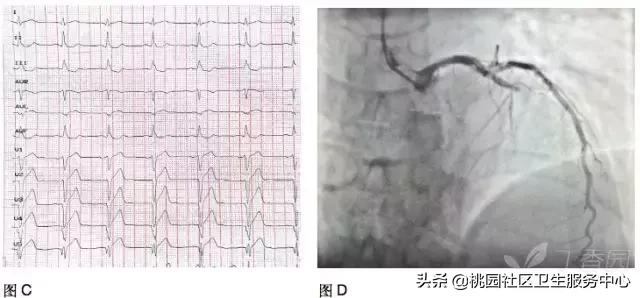

患者男,47 岁。血压高 20 余年,胸痛不适 1 年,再发 3 个月入院。A、B、C、D 图为同一时段不连续记录的动态心电图提示存在:T 波电交替(TWA)。诊断:变异型心绞痛。3 天后冠状动脉造影:前降支近段重度狭窄,对角支开口处重度狭窄,行 PCI 术好转。

A:*坐静**休息,窦性心律,ST-T 未见异常。

B:3 min 后,轻微闷痛,心电图 V3、V4 导联可见异常 J 波,V1~V5 导联 ST 段呈弓背型抬高伴 T 波直立高耸、ST-T 振幅呈高低交替。

C:35s 后,在 V1~V5 ST 段仍弓背抬高,第 4 个心搏为,出现室性早搏。

D:1 min 后,ST-T 已恢复正常。